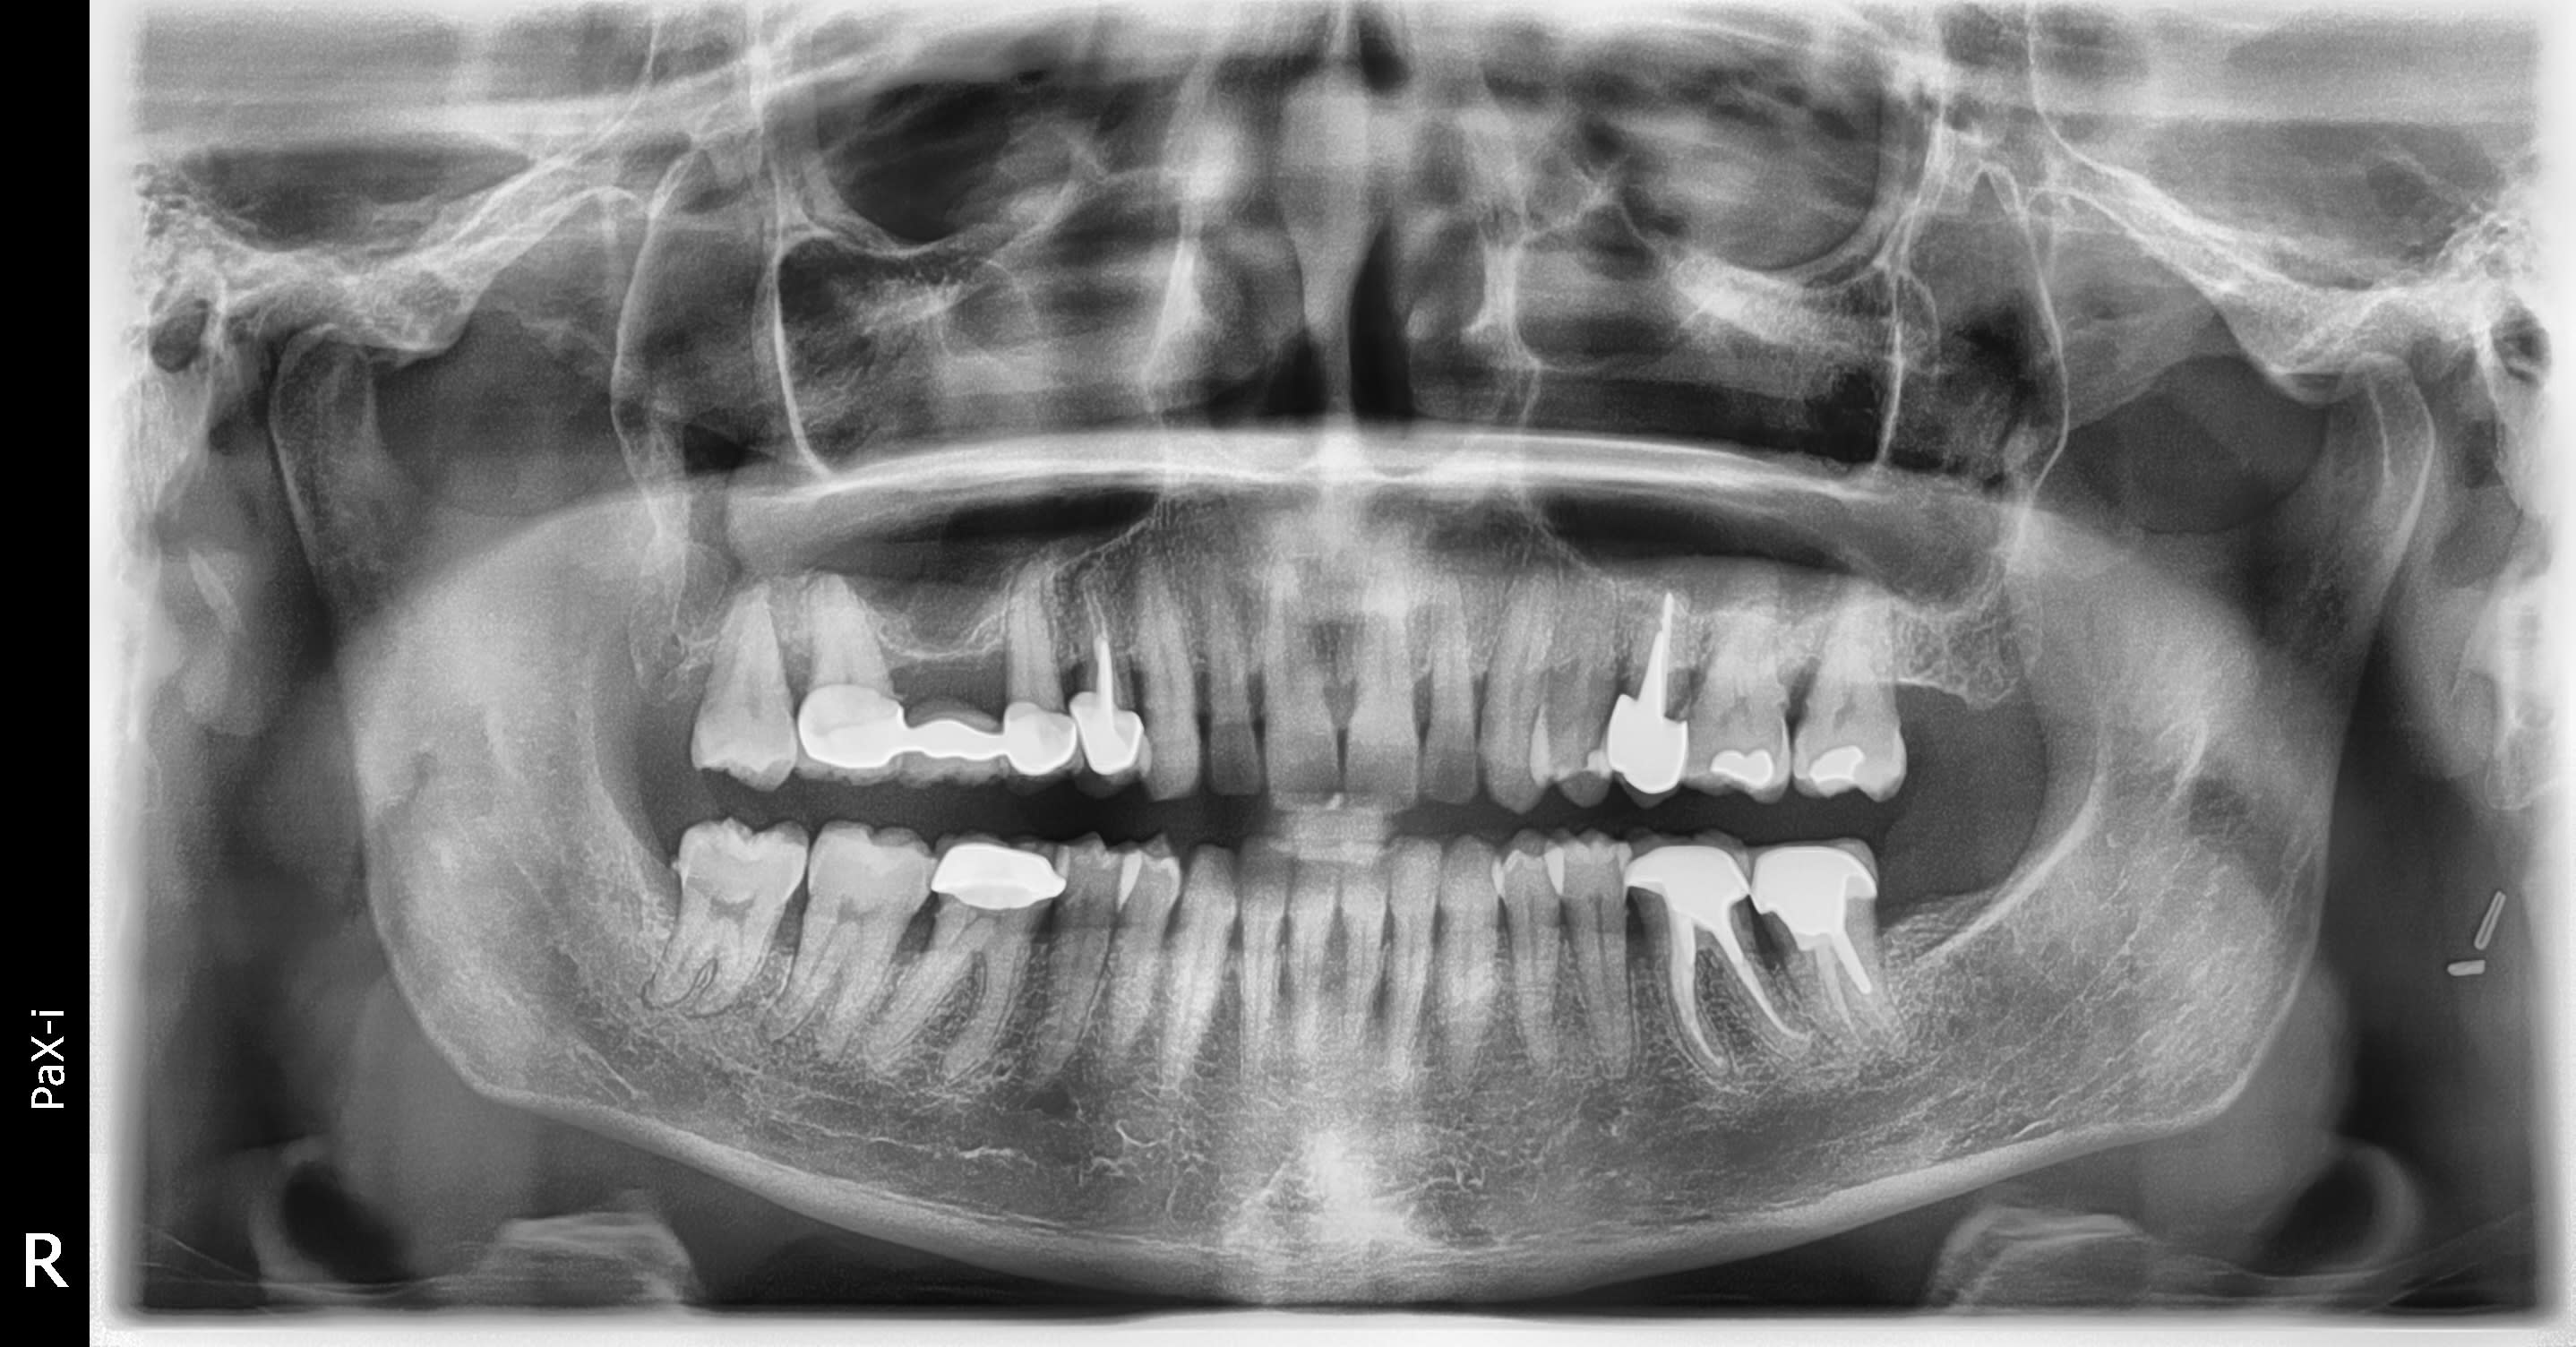

Les 17 15 48 et 46 sont vitales

14 25 37 36 asymptomatiques

Petites réactions péri-apicales sur 14 et 25

Désolé j'avais oublié la pano.

Les couronnes donc les endo ont +- 20 ans

A la pano, rien de scandaleux ! Peut-être, un détartrage.

Possible souci 46 au niveau joint coiffe dent en distal